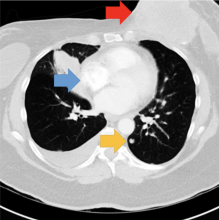

This video shows a computed tomography (CT) scroll through showing bowel ischemia and perforation (see arrows) due to superior mesenteric artery (SMA) thrombus in COVID-19 (SARS-CoV-2) patient. Mesenteric artery thrombosis (MAT) is a condition involving occlusion of the arterial vascular supply of the intestinal system and is a severe and potentially fatal illness.

Superior mesenteric artery thrombosis (Red arrow) complicated by bowel ischemia and perforation in a 54-year-old man who presented to the emergency department with abdominal pain and was diagnosed with COVID-19. Contrast-enhanced CT images of the abdomen and pelvis show mucosal hyperenhancement involving the small bowel (green arrows).

Read more in the article Multisystem Imaging Manifestations of COVID-19, Part 1: Viral Pathogenesis and Pulmonary and Vascular System Complications.

Case example from Margarita Revzin, M.D., associate professor of radiology and biomedical imaging, Yale School of Medicine.